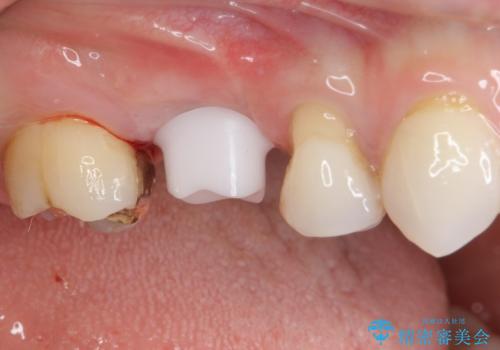

機能性と清掃性、更には審美性も考慮し、土台となるアバットメントにはジルコニアカスタムアバットメントを採用しました。

ジルコニアカスタムアバットメントは、歯肉ラインに金属が見えにくいというだけでなく、クラウンを装着する土台の形が天然歯と近い形態となるため、清掃性が高く歯肉が腫れにくいというメリットがあります。